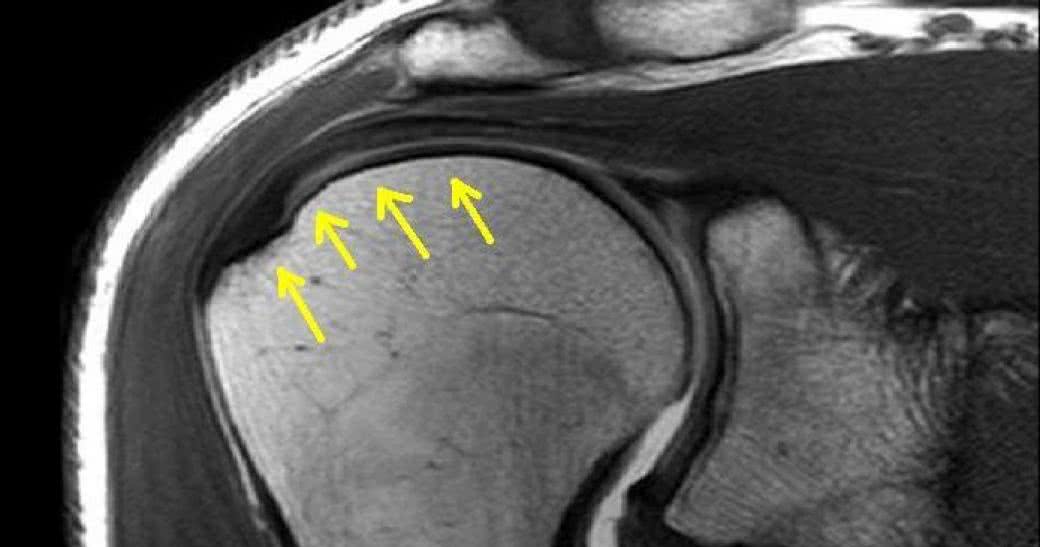

Kluczową rolę w profilaktyce chorób stawów odgrywa dieta. Kondycja stawów w dużej mierze zależy od stanu chrząstki stawowej, która pokrywa powierzchnie stykających się kości, ułatwiając poślizg i zapobiegając ich ścieraniu. Dlatego zadbaj o to, by w Twoim jadłospisie regularnie znajdowały się produkty bogate w białko (budulec dla chrząstki stawowej) i wapń, który wraz z fosforem buduje kości.